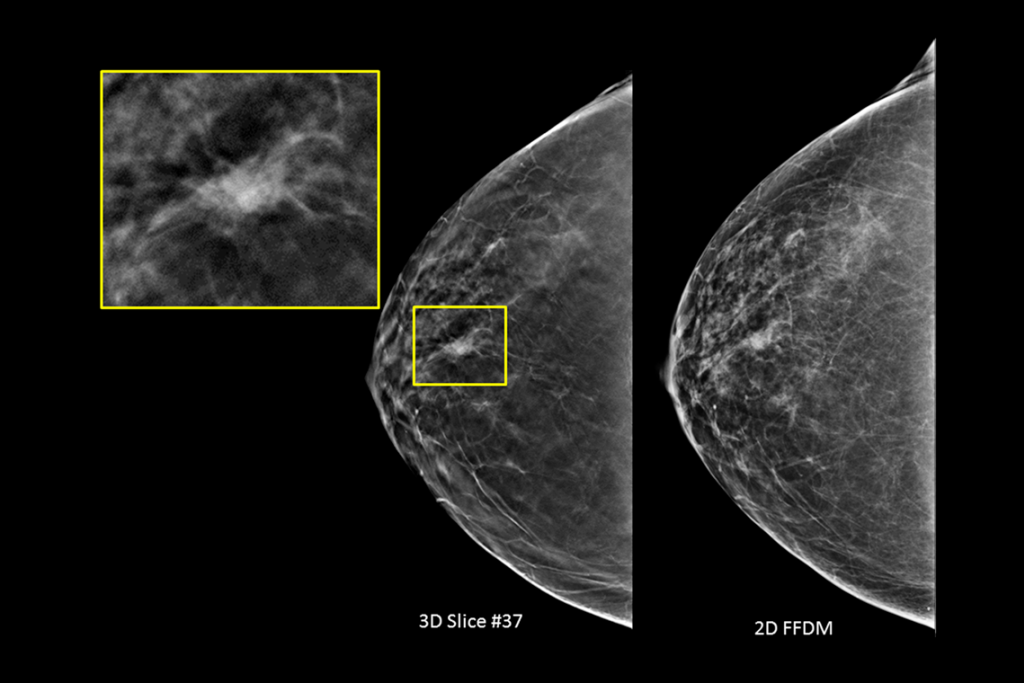

Immagini cliniche di una mammografia

Immagini cliniche di una mammografia con lesione sospetta